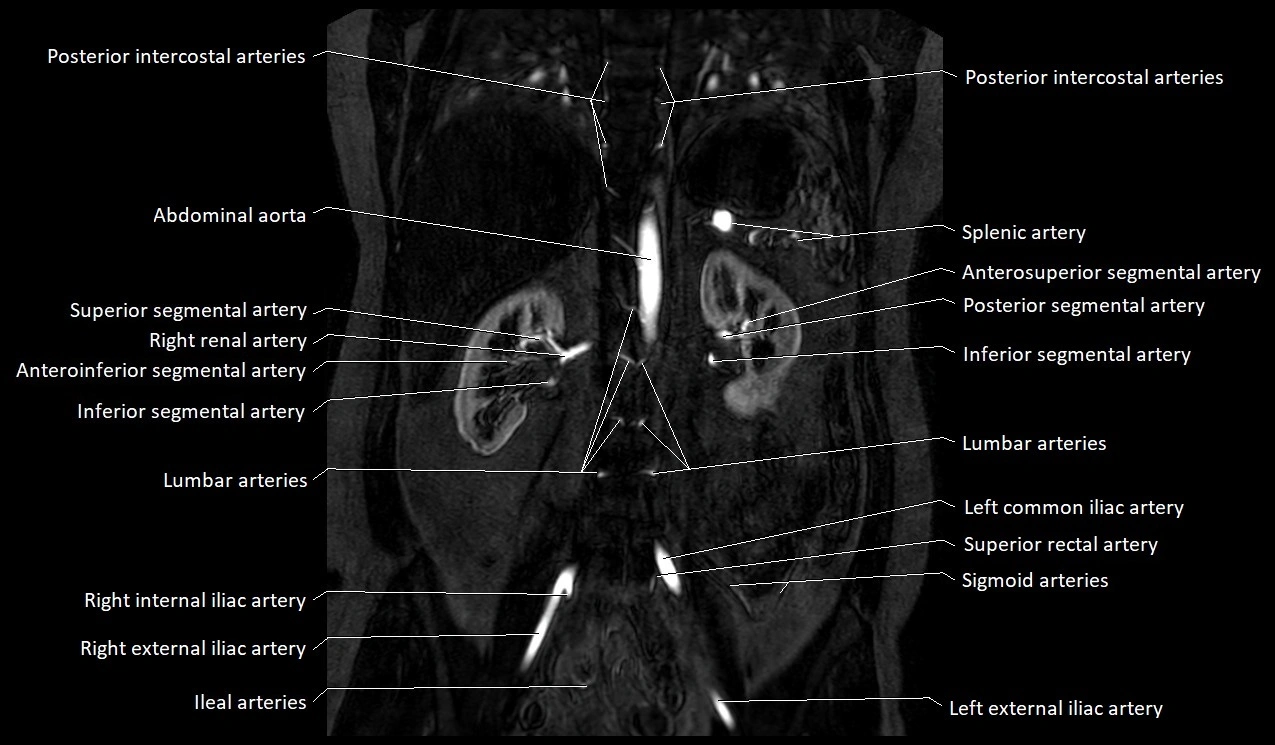

MRA Pelvis with Gadolinium:

-

Clearly delineates the origin, course, and anastomoses of the accessory obturator artery

Identifies connection with inferior epigastric artery, external iliac artery, or obturator artery

Excellent for detecting vascular variants prior to surgery

Useful in mapping pelvic vasculature in trauma, tumor embolization, or preoperative planning